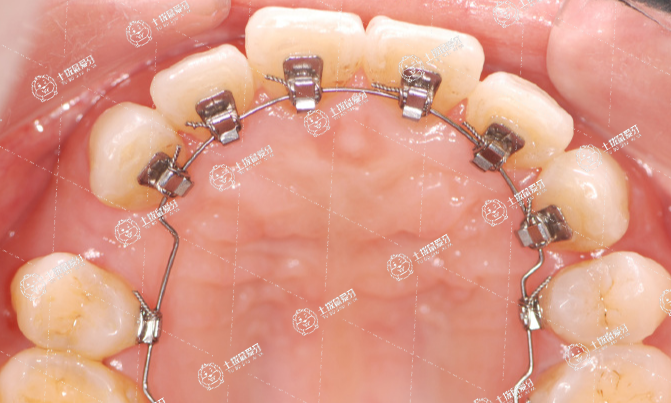

舌側(cè)矯正是一種將矯治器粘接于牙齒舌側(cè)上進(jìn)行牙齒矯正治療的正畸技術(shù)。舌側(cè)矯正從外觀上看不到任何的正畸治療裝置,不僅能有效的避免成年人進(jìn)行牙齒矯正時(shí)成為“鋼牙妹”的尷尬,而且還能達(dá)到比唇側(cè)矯正更精確的矯正效果,是真正意義上的“隱形矯正”技術(shù)。舌側(cè)矯正技術(shù)一經(jīng)問世,就受到了演員、律師、教師等美觀或職業(yè)要求較高患者的廣大歡迎,也是目前牙齒矯正領(lǐng)域中最為高端、復(fù)雜的矯正技術(shù)。

舌側(cè)正畸的矯治器全部安裝于牙齒的舌側(cè)面進(jìn)行正畸治療,因此旁人無法看見托槽鋼絲,可以做到完全隱形,讓牙齒悄然排列整齊。

4.不損傷牙面